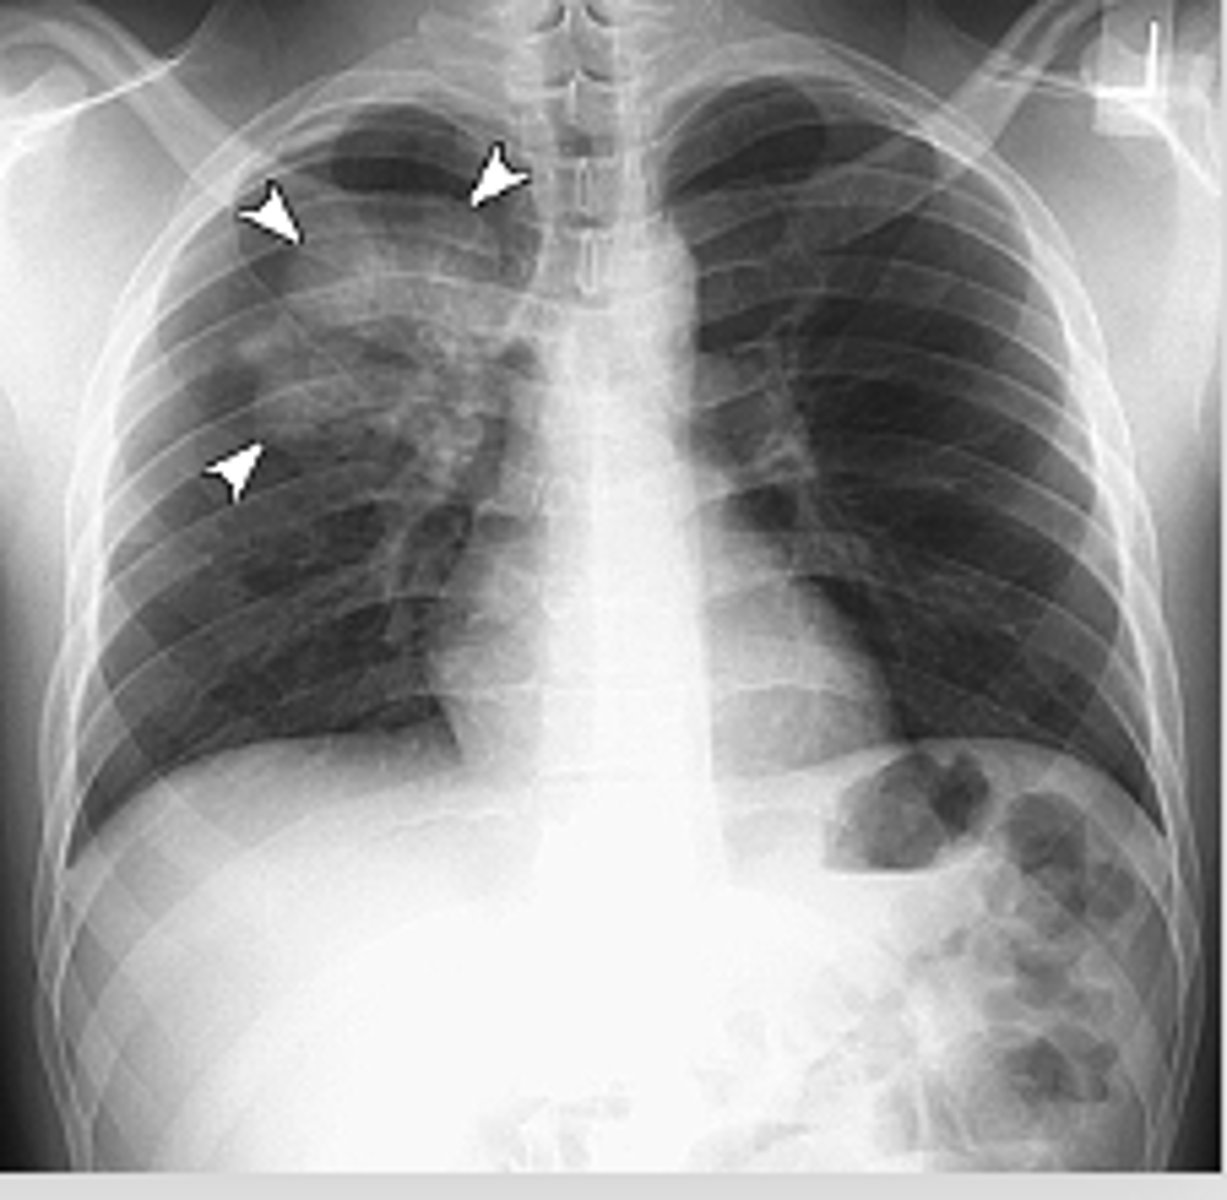

Small cell carcinomas

often present as an indistinct hilar or mediastinal mass. (pic: R hilar and paratracheal region)

<p>often present as an indistinct hilar or mediastinal mass. (pic: R hilar and paratracheal region)</p>